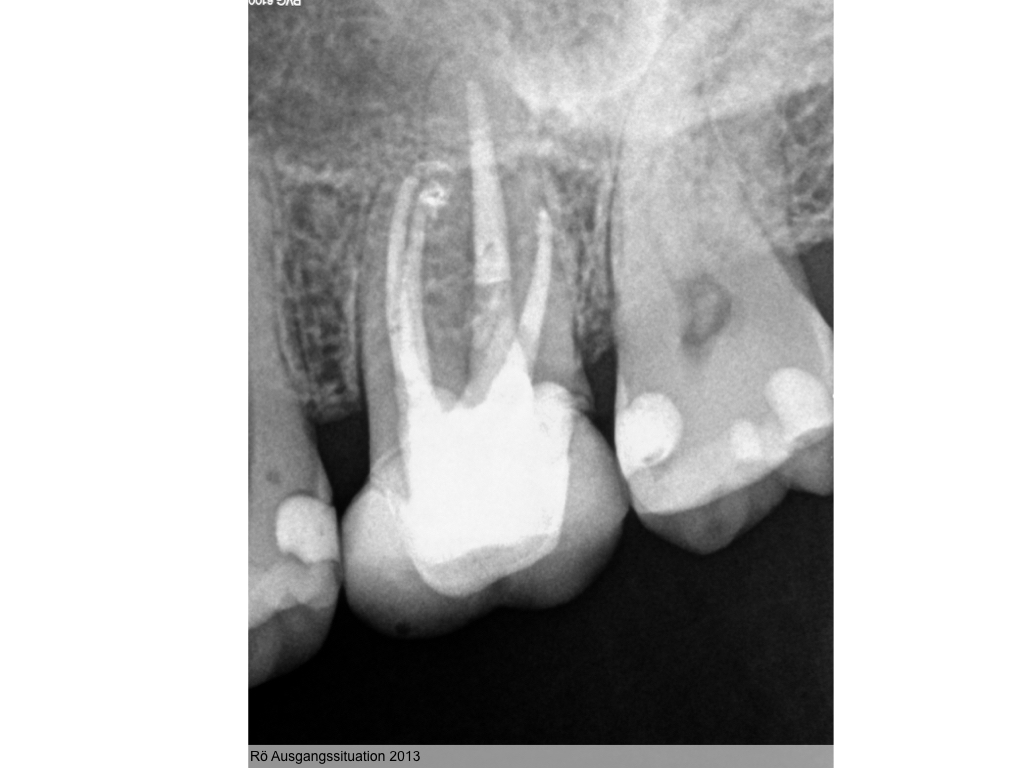

Heilung oder was?